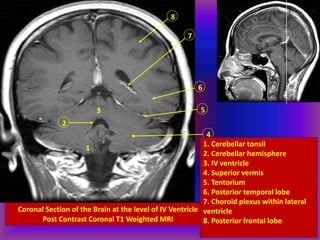

Coronal Section of the Brain at the level of IV Ventricle

Post Contrast Coronal T1 Weighted MRI

8

7

6

5

4

3

2

1

Identify anatomical structures

1 - 8

1. Cerebellar tonsil

2. Cerebellar hemisphere

3. IV ventricle

4. Superior vermis

5. Tentorium

6. Posterior temporal lobe

7. Choroid plexus within lateral

ventricle

8. Posterior frontal lobe